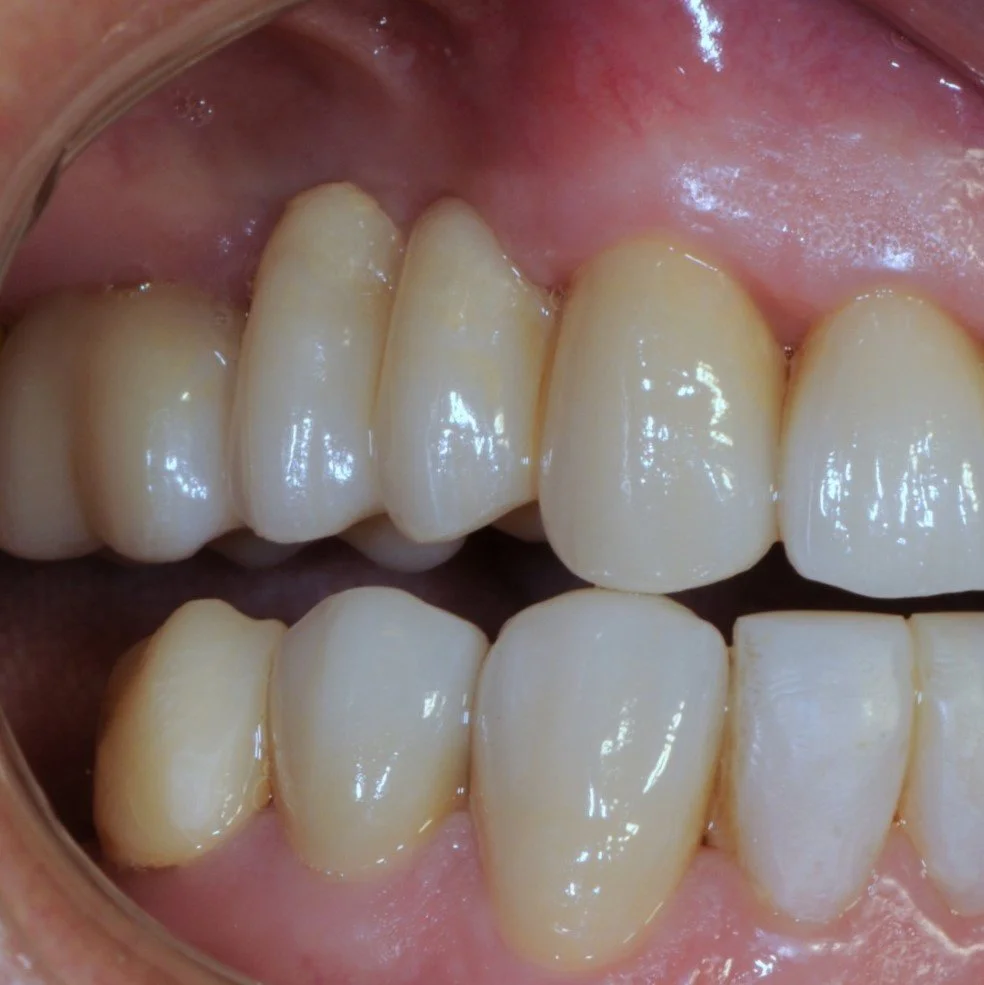

THE COMPLETED CROWN AND BRIDGE AFTER FINAL CEMENTATION AND A PROTECTIVE FORWARD BITE.

THE LEFT VIEW ILLUSTRATES A HUMAN LEFT PROTECTIVE BITE WITH A VERTICO-LATERAL JAW MOVEMENT.

THE FINAL PHOTO IN HINGE BITE WITH GREATLY IMPROVED AESTHETICS.